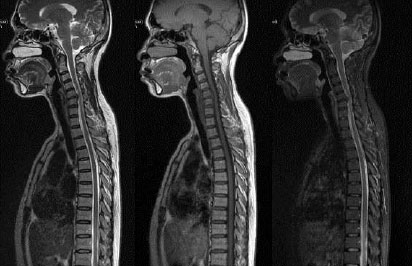

医学影像科是以胸部影像为特色,集检查、诊断、治疗于一体的临床检查科室,包括普通放射学,CT和MRI三部分。除了在肺结核和胸部肿瘤方面具有丰富的诊断经验和高超的鉴别水平外,还广泛的开展颅脑结核、骨结核和其它肺外结核的影像诊断、鉴别诊断,也开展CT引导下活检及介入治疗等项目。团队组成目前,我院医学影像科共有工作人员48人。其中诊断医师18人,正高职称5人,副高职称2人,中级职称5人,住院医师6人;技术人员20人,包括副主任技师1人,主管技师8人,技师6人,技士5人;主管护师8人;工程师2人;我们拥有全国知名的专家团队,在学术水平上达到国内一流水平。仪器设备1. 传统影像科:(1)CT3台:超高端256排螺旋CT 1台 、 64排128层螺旋CT 和64排螺旋CT各1台 。(2)核磁1台:3T核磁共振。(3)DR 3台。(4)乳腺钼靶1台。(5)…更多>>